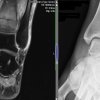

Undisplaced Fracture – Distal Tibial Metaphysis | Cases

Published on Jun 9, 2020

Female, 45. Started running 4 months ago. Gradually building distance. 3 week ago developed significant ankle swelling, pain and difficulty weight bearing after an 8 mile run. No history of injury X-ray – NAD Exam Ankle swollen Tender on palpation over left medial malleolus and along tibial shaft. MRI Coronal Saggital T1 There is an undisplaced [...] Read more